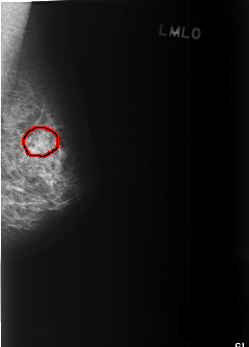

C_0372_1.LEFT_MLO

LEFT_MLO LINES 5552 PIXELS_PER_LINE 3976 BITS_PER_PIXEL 12 RESOLUTION 50 OVERLAY

FILE: C_0372_1.LEFT_MLO.OVERLAY

TOTAL_ABNORMALITIES 1

ABNORMALITY 1

LESION_TYPE MASS SHAPE OVAL MARGINS ILL_DEFINED

ASSESSMENT 3

SUBTLETY 3

PATHOLOGY BENIGN

TOTAL_OUTLINES 1

BOUNDARY